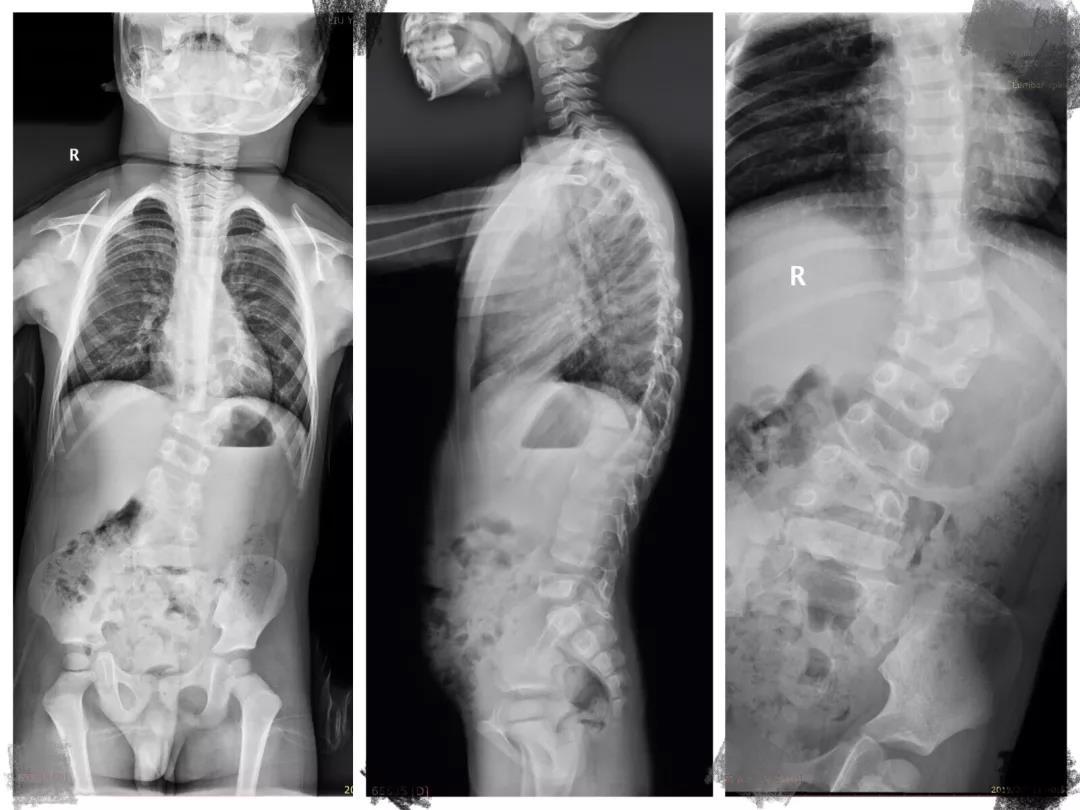

脊柱侧弯是一种复杂的三维脊柱畸形,按照年龄阶段又可以划分为:婴儿型

「婴儿型特发性脊柱侧弯」相当罕见,且多会自己恢复正常,只有少部人

"孩子是先天性脊柱侧弯,考虑到他的年龄,身体发育等综合情况,我们建议